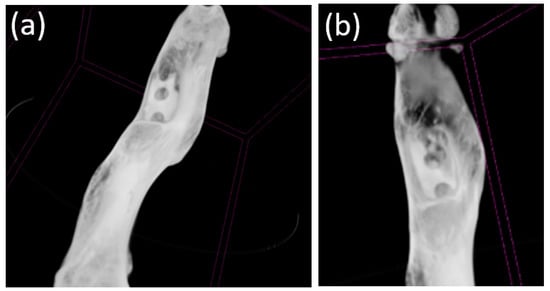

3.4. Cone Beam Computed Tomography